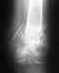

Трехлодыжечный перелом левой голени

29 июля получила травму голеностопного сустава: двухлодыжечный перелом левой голени, перелом заднего края большеберцовой кости, вывих стопы кнаружи и кзади, экстренно попала в больницу, где было сделано закрытое вправление и наложен гипс.

Был предложен остеосинтез, от которого я отказалась по причине того, что на этой ноге стоит эндопротез тазобедренного сустава, который был поставлен после множества операций вследствие тяжелой травмы таза. Через неделю провели ещё одно закрытое вправление, чтобы максимально исправить смещение, и наложен полимерный бинт (пластиковый ортез). После выписки состояние к/отломков удовлетворительное, была отправлена на лечение в больницу по месту жительства. Прошло 8 недель, в этой больнице отказываются делать снимки,мою ситуацию никак не комментируют. Так как в прошлый раз встать на ноги мне помогли врачи ГФУН УНИИТО на Банковском, хотелось бы пройти очную консультацию в данном лечебном заведении (там же хранится моя огромная история болезни). Так как направления у меня нет, интересует вопрос: можно ли пройти консультацию платно, сделать снимки? В каком отделении это лучше сделать (на Банковском, Студенческой или Московской)? Огромное спасибо за ответ.